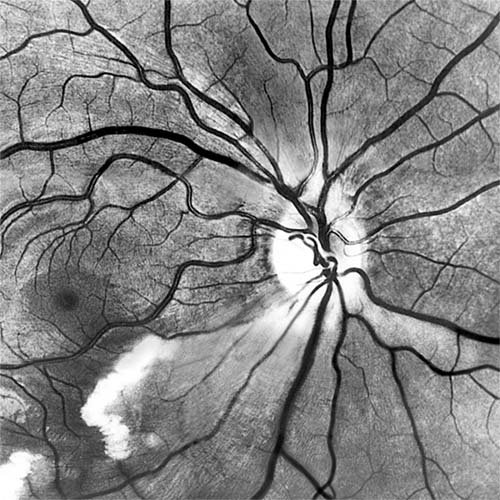

Figure 15-12

Figure 15-12: A: Fluorescein angiogram of left fundus in a patient with chronic ocular ischemia secondary to Takayasu's disease. Note capillary dilation, leakage of dye, retinal hemorrhages, cotton-wool spots, and neovascularization of the optic nerve head. B: Fluorescein angiogram, showing leakage at optic disk and macula in a patient with chronic ocular ischemia secondary to dural arteriovenous fistula.

Carotid Cavernous Fistula

Carotid cavernous fistula results from a communication between the carotid artery or its branches and the cavernous sinus, producing characteristic vascular signs. Direct carotid fistulas are usually acute, florid, and posttraumatic, whereas fistulas from dural vessels are usually chronic, mild, and not associated with trauma. Clinical features include elevated intraocular pressure, dilated conjunctival vessels, dilated retinal vessels with hemorrhages and fluorescein leakage (Figure 15-12B), ophthalmoplegia (usually lateral rectus), and bruit. computed tomography (CT) and magnetic resonance imaging (MRI) show thickened ocular muscles and a dilated superior ophthalmic vein. The condition must be differentiated from thyroid eye disease, and interventional radiology is the ultimate diagnostic and therapeutic resource.